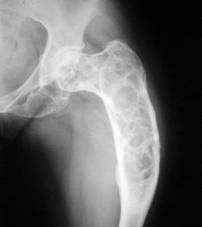

TUMORA CU MIELOPLAXE (OSTEOCLASTOM)

Clinic, tumora cu celule gigante se dezvolta lent. Primul simptom este tumefactia localizata la o epifiza care este putin dureroasa; rar debuteaza prin fractura pe os patologic.

Radiologic

osteoclastomul central - apare ca o zona de osteoliza epifizara cu margini net delimitate spre partea sanatoasa a osului. Pe masura ce se dezvolta, lateste si deformeaza epifiza, subtiaza corticala dând osului un aspect suflat.Corticala nu este întrerupta, periostul nu este îngrosat si nu sunt invadate partile moi atât timp cât tumora este benigna. Ruperea corticalei este semn de degenerare maligna.